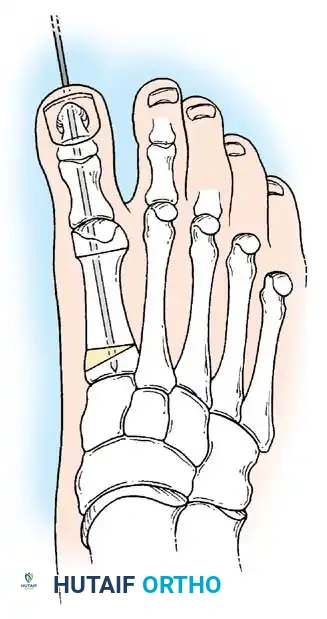

Modifi ed McBride Bunionectomy TECHNIQUE 78-1

SKIN AND CAPSULAR INCISION

• With the patient supine and a tourniquet on the limb, extend a midline, straight, medial incision from the middle of the proximal phalanx to 2 cm proximal to the junction of the medial eminence with the metatarsal shaft (Fig. 78-13). This incision usually is in an internervous plane between the most medial branches of the superfi cial peroneal nerve dorsally and the medial proper digital branch of the medial plantar nerve plantarward. (McBride recommended a single incision beginning at the fi rst web space and extending proximally and medially across the metatarsal, ending on the medial side of the fi rst metatarsal proximal to the exostosis.)

• Make a longitudinal capsular incision (the original McBride capsular incision was transverse) 3 to 4 mm plantar to the line of the skin incision (Fig. 78-14).

• By sharp dissection, raise the periosteum and the capsule dorsally and plantarward from the base of the proximal phalanx to the proximal edge of the medial eminence (Fig. 78-15). At the proximal end of the medial eminence, avoid releasing the proximal bony attachments of the medial capsule on the metatarsal neck (especially in the dorsal direction) in an attempt to expose the medial eminence. To ensure adequate exposure without disruption of this proximal attachment, a longitudinal capsular incision is suggested.

• Elevate the capsule by sharp dissection dorsalward and plantarward to expose the dorsal aspect of the metatarsal head, the entire medial eminence, and the plantar plate. A periosteal elevator is not recommended because of the possibility that the proximal attachments of the capsule may be released.

• Grasp the hallux in one hand and displace the proximal remnant medially so that, under direct vision, two longitudinal 0.062-inch Kirschner wires can be inserted.

• Hold the interphalangeal joint straight while drilling the wires from proximal to distal, emerging a few millimeters plantar to the nail plate.

• Return the foot to the corrected position, and drill the wires into the metatarsal head.

• While holding the metatarsal as far laterally as possible, cross the joint, and drive the wires out the plantar cortex just proximal to the head, while holding the hallux in 10 to 15 degrees of extension, neutral abduction, adduction, and rotation, and no translation dorsally or plantarward on the metatarsal head. The wires should penetrate only 2 to 3 mm past the cortex to avoid tenderness over the wires with weight bearing.